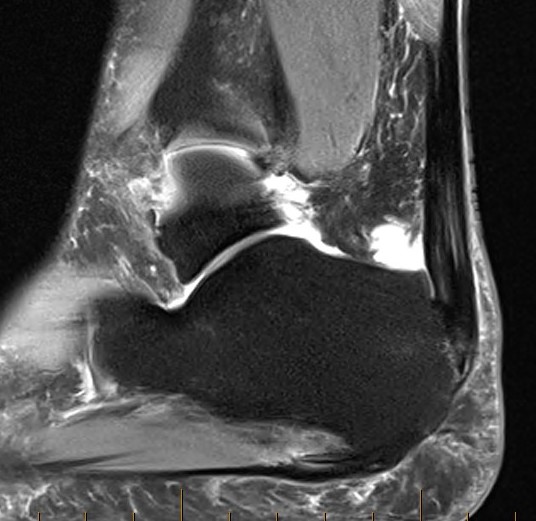

MRI

Retrocalcaneal bursitis with Haglund's

Partial tearing at insertion with retrocalcaneal bursa

Tendon thickening, Haglund's deformity and retrocalcaneal bursa

MRI grading

- Grade I: 6 - 8 mm thickening

- Grade II: > 8 mm tendon thickness with < 50% tendon degeneration

- Grade III: > 8 mm tendon thickness with > 50% tendon degeneration